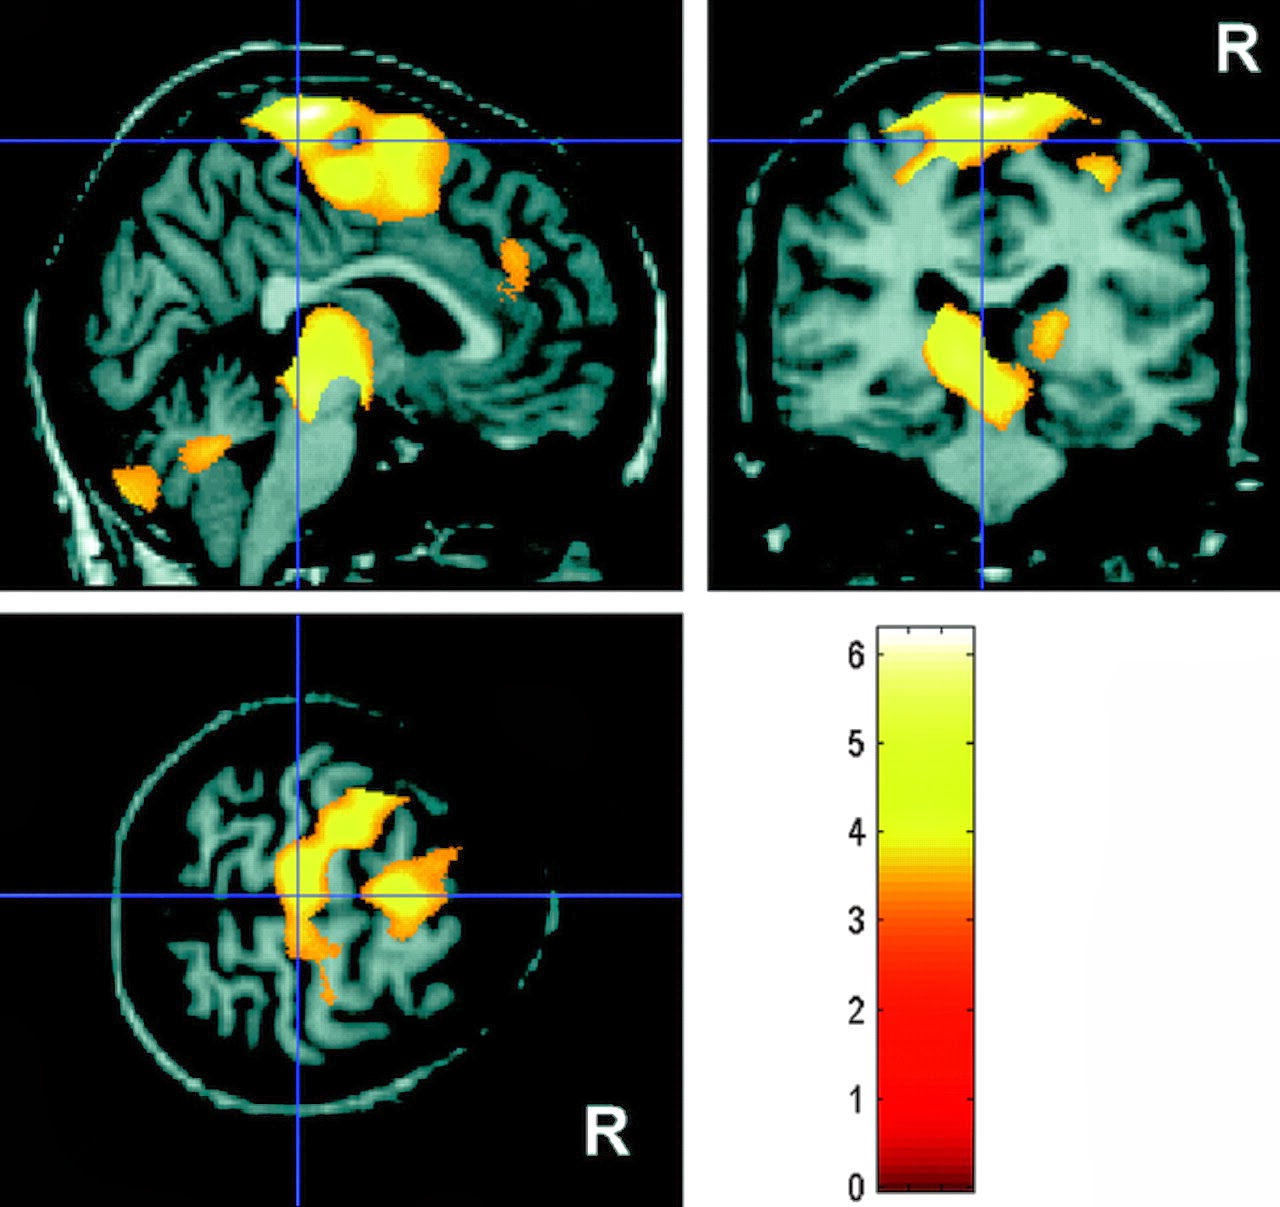

Phenylketonuria (PKU)